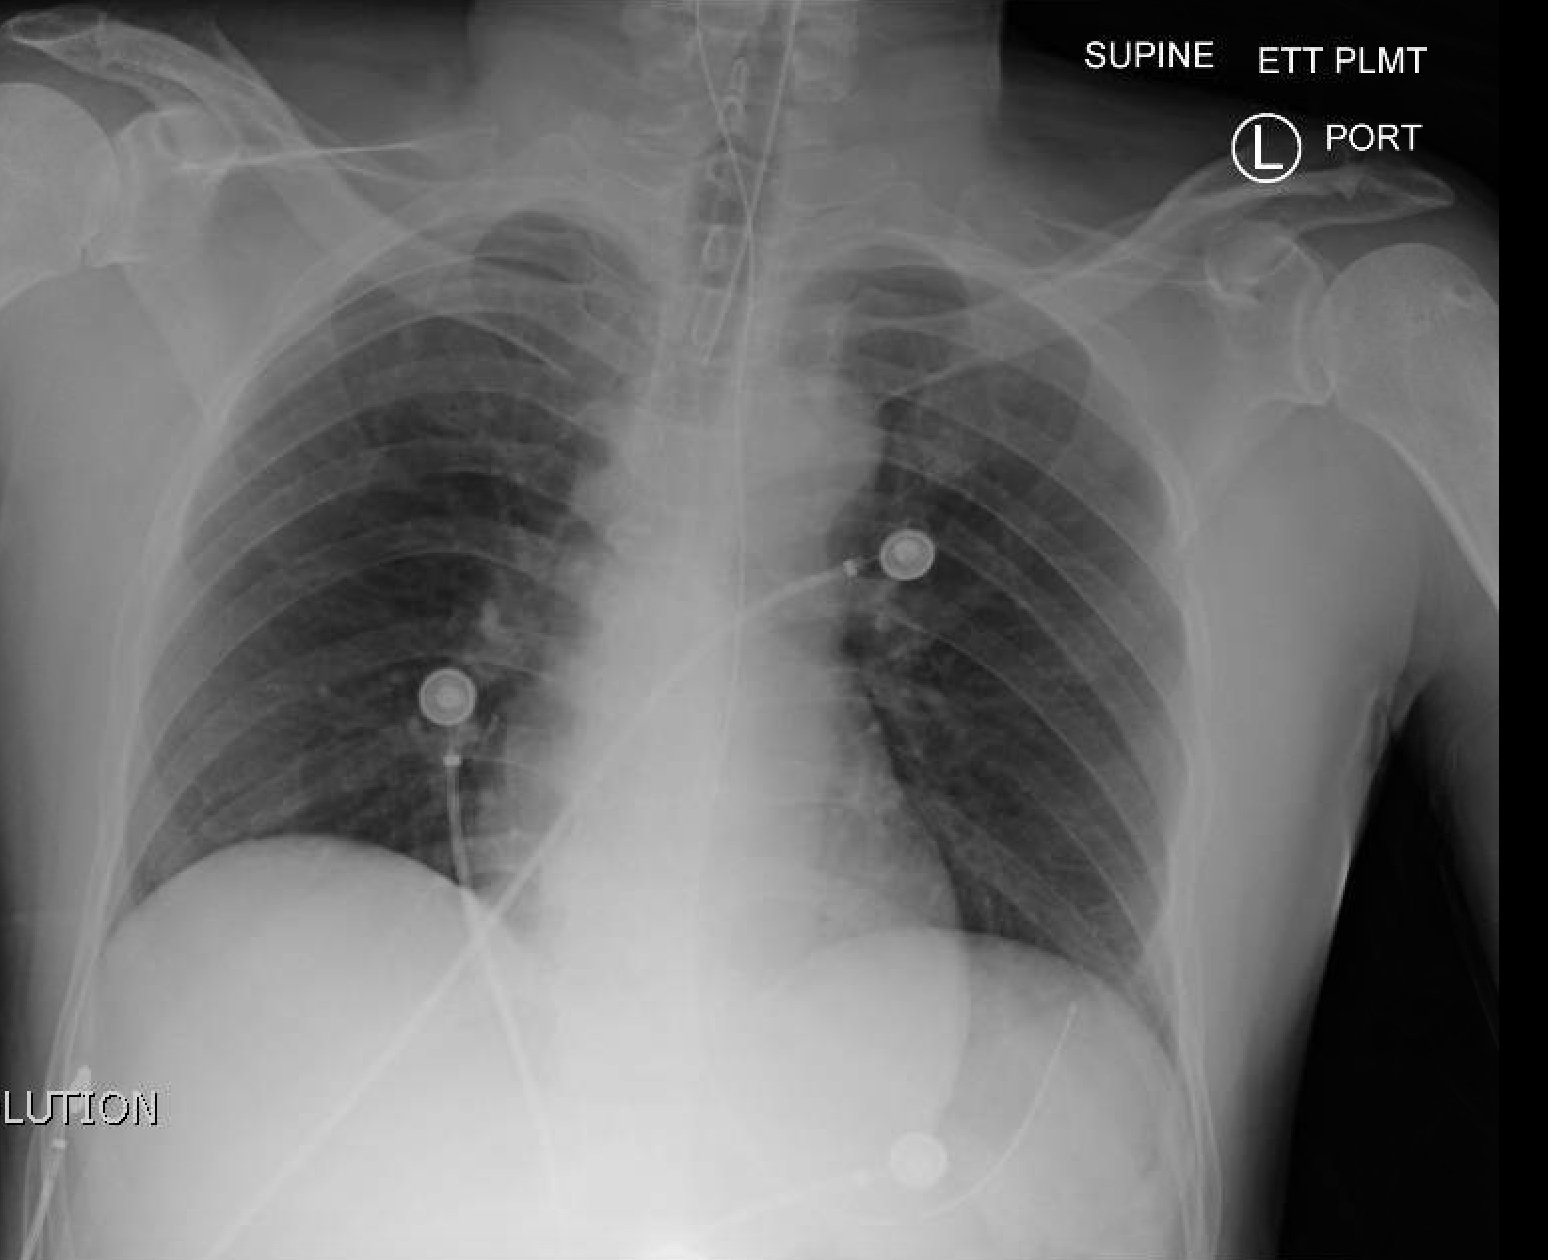

Normal CXR and Post-Intubation CXR

post intubation chest x-ray

Normal chest x-ray

radiology, normal, intubation, CXR, chest, respiratory, respiratory failure, AP, ETT, post-intubation

X-Ray